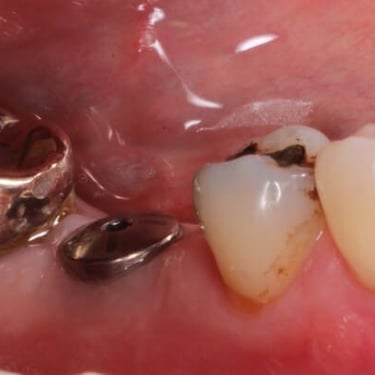

Implantes dentales fracasados

Los implantes dentales fracasados son aquellos que no se han integrado correctamente con el hueso o han desarrollado complicaciones postoperatorias.

Los pacientes pueden notar movilidad en el implante, dolor o inflamación.

El tratamiento puede incluir la extracción del implante fallido y la preparación para un nuevo implante.